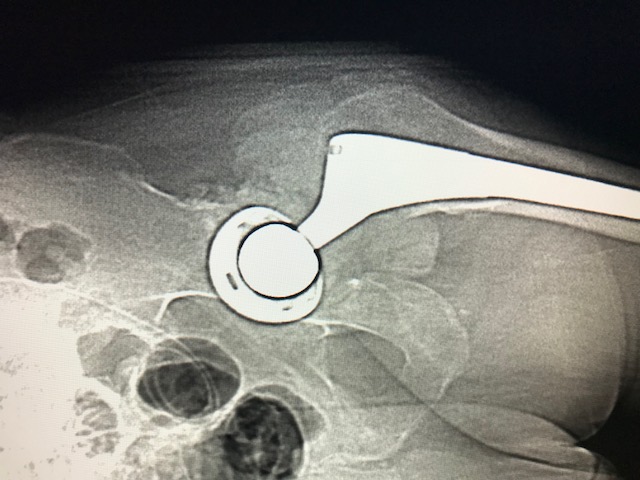

Figure 4 for case Tumoral calcinosis ( RID5202 )

Figure 4

Discussion

Tumoral calcinosis likely, given hypercalcemia, peritoneal dialysis catheter, lack of lymphocytosis on the aspiration and lack of soft tissue changes; really points away from pseudotumor AVAL ATR.

Diagnosis

Tumoral calcinosis ( RID5202 )